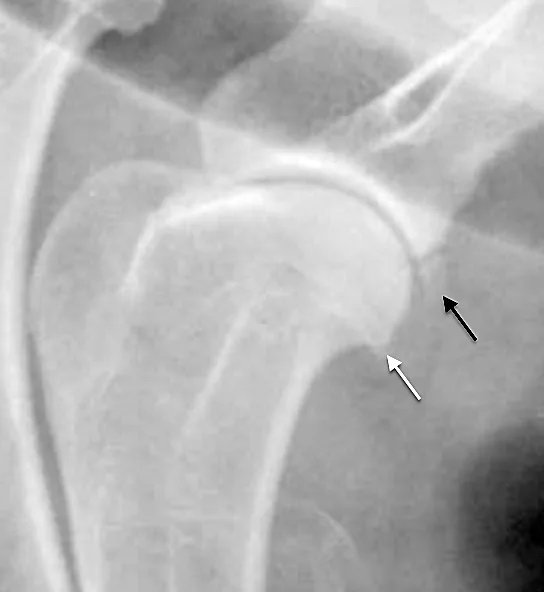

FIGURE 3

Lateral radiograph of a mature shoulder with a separate center of ossification in the caudodistal scapula (black arrow). Minimal osteophytosis of the caudal aspect of the humeral head (white arrow) is also present.

Degenerative joint disease affects the entire joint, but the caudal humeral head is a common site of osteophytosis development. Degenerative joint disease appears radiographically as well-defined, irregularly shaped new bone formation on the caudal aspect of the glenoid cavity or the caudal humeral head. In many dogs, a small, separate, triangular center of ossification may be present and associated with the caudodistal scapula (caudal glenoid cavity; Figure 3).2 This should not be confused for degenerative joint disease.